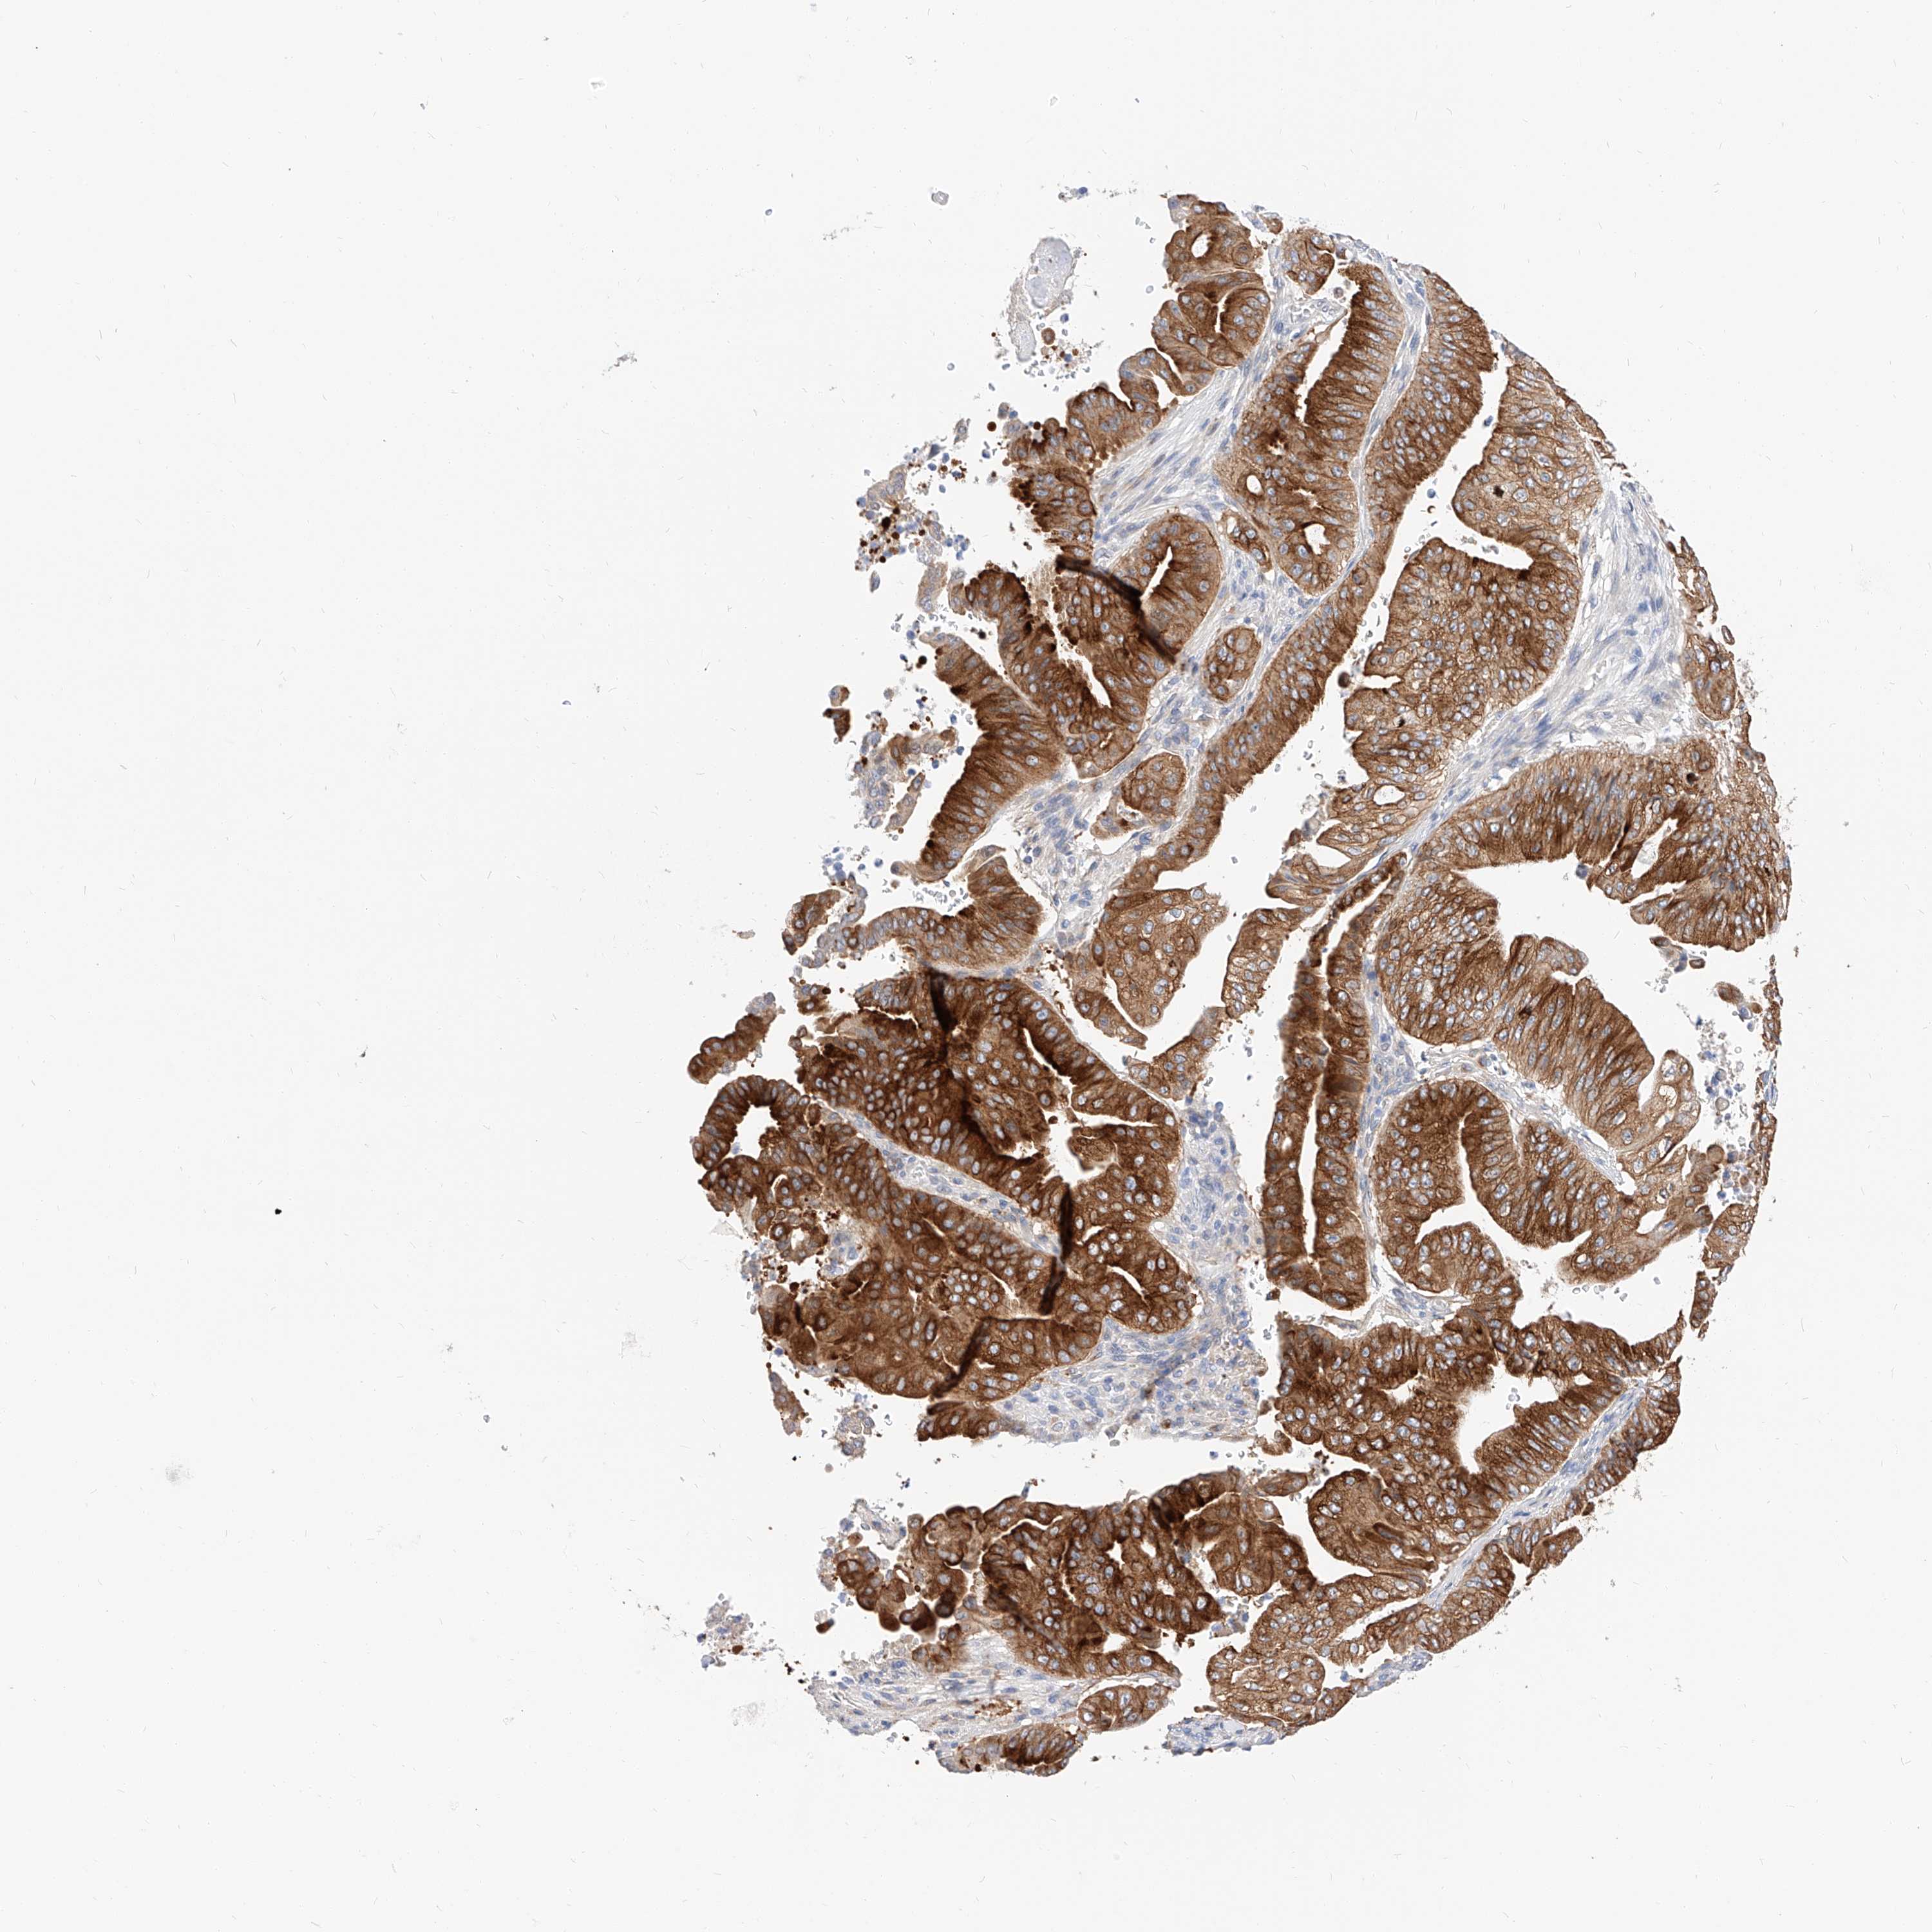

PANCREATIC CANCER - Protein expressioni

A mouse-over function shows sample information and annotation data. Click on an image to view it in a full screen mode. Samples can be filtered based on level of antibody staining by selecting one or several of the following categories: high, medium, low and not detected. The assay and annotation is described here.

Note that samples used for immunohistochemistry by the Human Protein Atlas do not correspond to samples in the TCGA dataset.

Antibody stainingi

Antibody staining in the annotated cell types in the current human tissue is reported as not detected, low, medium, or high, based on conventional immunohistochemistry profiling in selected tissues. This score is based on the combination of the staining intensity and fraction of stained cells.

Each image is clickable and will lead to virtual microscopy that enables deeper exploration of all samples and also displays staining intensity scores, fraction scores and subcellular localization as well as patient and tissue information for each sample.

Antibody HPA029712

Antibody HPA029713

Staining

High

Medium

Low

Not detected

Intensity

Strong

Moderate

Weak

Negative

Quantity

>75%

75%-25%

<25%

None

Location

Nuclear

Cytoplasmic/membranous

Cytoplasmic/membranous,nuclear

Adenocarcinoma, NOS